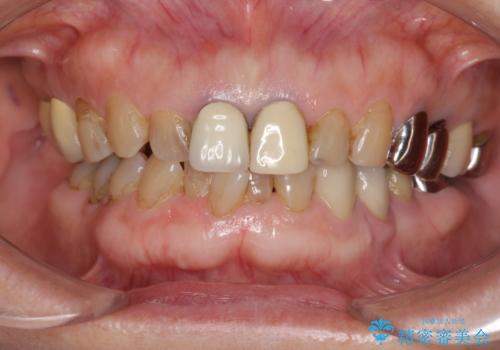

前歯の審美改善

- 70代女性

- 孫娘の結婚式に合わせて前歯を綺麗にして写真映りをよくしたいと来院されました。

結婚式に合わせて根管治療からのやりかえを短期集中治療で計4回で終える計画を立てます。

- 40万円(仮歯・ファイバーコア・ジルコニアクラウン×3)費用は治療当時の料金となります